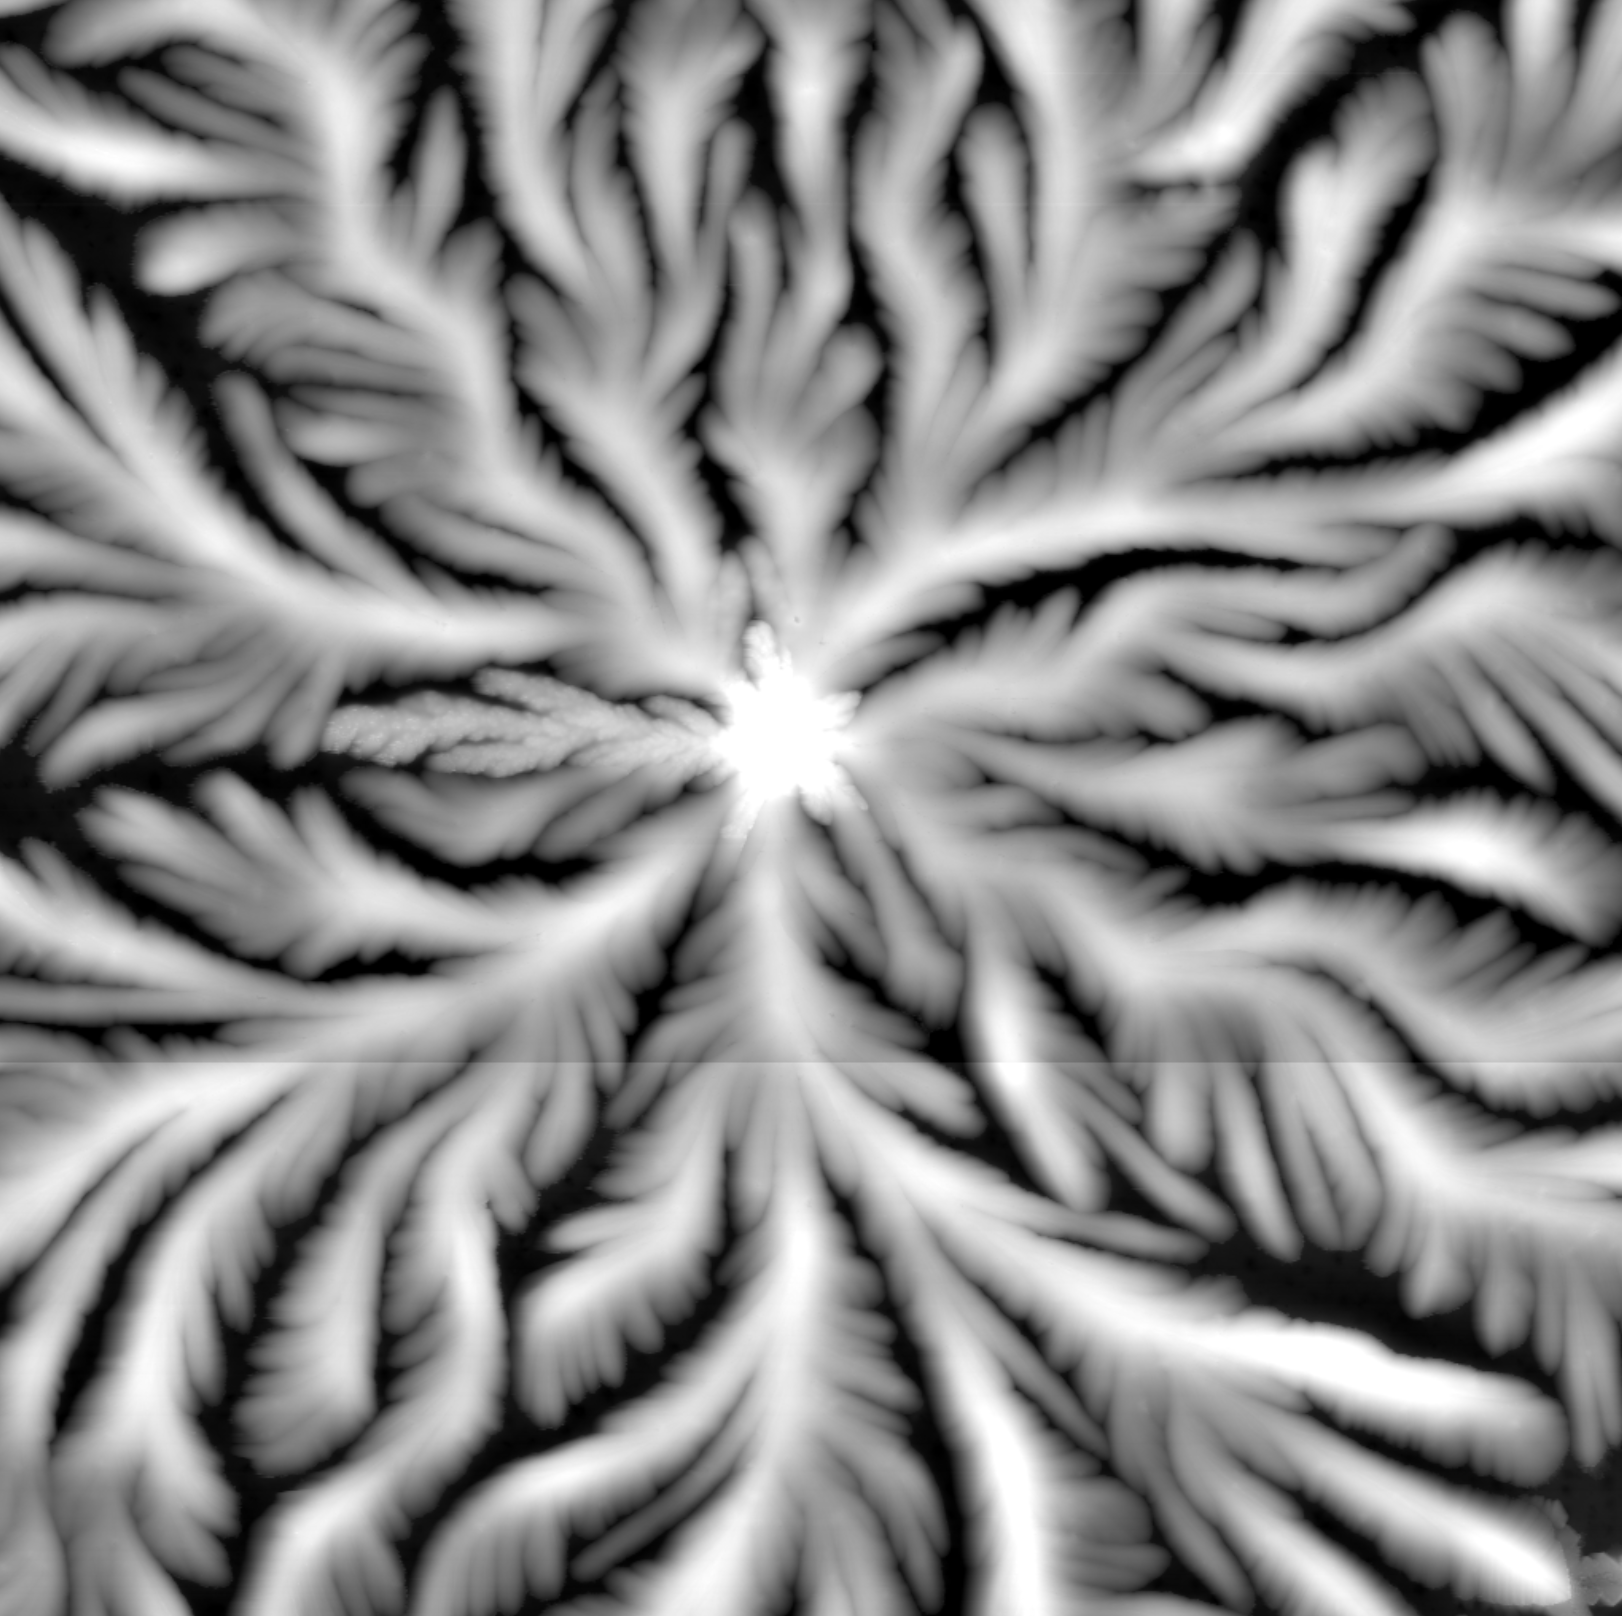

AFM scan of a healthy dried tear

Healthy

baseline

Even branching, soft radial symmetry, clean edges.